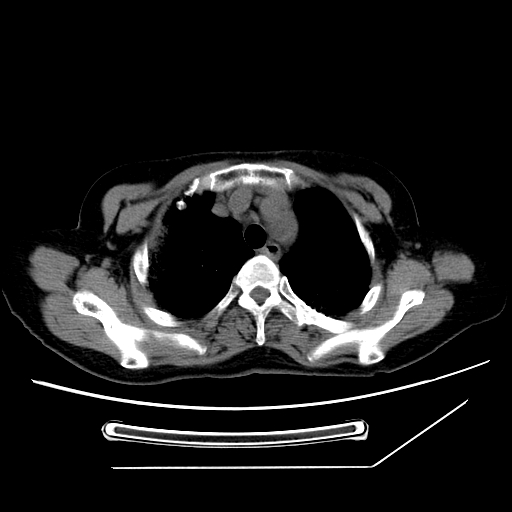

标题: CT25393:病人45岁,咳嗽,吐黄痰带血丝,发热,胸闷月余 [打印本页]

标题: CT25393:病人45岁,咳嗽,吐黄痰带血丝,发热,胸闷月余

1、左肺中央型肺癌并双肺弥漫性转移   2、双肺部感染    3、肺大泡     4、左侧胸腔积液

双侧肺弥漫性病变,可见“空泡征”及“蜂窝征”,考虑肺泡癌可能性大,左侧胸腔积液,考虑胸膜受累可能!

考虑肺泡癌,建议排除感染。

考虑肺泡癌

1)不排除肺泡癌可能。2)左侧胸腔积液。